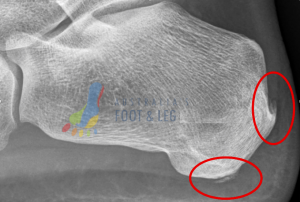

- The number one muscle that is tight in at least 95% (anecdotal figure) of patients is the calf muscle. As a result on imaging we can typically see spurring, or at least excess bone deposit at the rear of the heel where your achilles tendon attaches to the heel bone. You can find an example of this shown on the foot x-ray below highlighted by the red circle.

- the next common muscles that are tight in many patients experiencing heel pain are the arch muscles. Please be aware there are multiple arch muscles in the foot – here we’re over-simplifying the topic for ease of illustration but many share a similar attachment point at the bottom of the heel bone. You can find an example of this shown on the foot x-ray below highlighted by the red circle.

- the final point that is rarely seen by itself but still worth a mention as it is a sign of long-standing plantar fascia attachment irritation of the heel bone is what we call the plantar fascial heel spur. This attachment point is the true attachment of the plantar fascia and irritation here is a sign of excessive strain through the plantar fascia. Bear in mind your plantar fascia is a strong ligament (bone to bone not muscle to bone with a tendon) so when this is pulling excessively your foot muscles have ‘given up’. You can find an example of this shown on the foot x-ray below highlighted by the arrow pointing at the red circle.